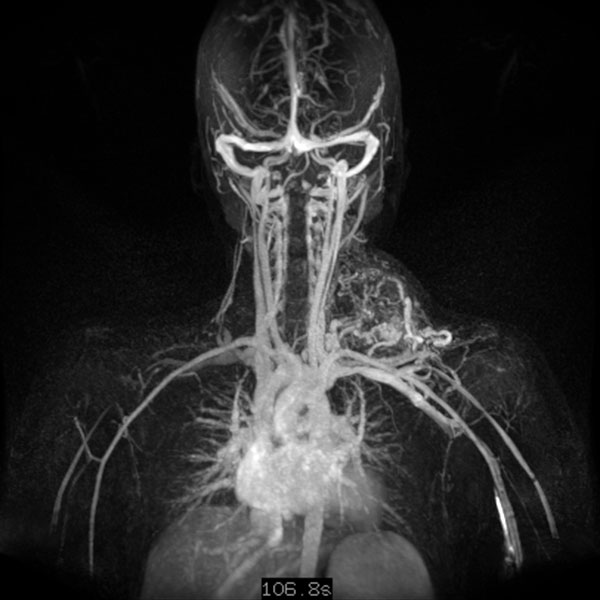

Dynamische, kontrastmittelunterstützte, zeitlich hochaufgelöste MR-Angiographie 5 Tage nach Embolisation; Darstellung in der Spätphase 107 s nach intravenöser Kontrastmittelapplikation. Auch nach diesem langen Delay zeigt sich keine Restperfusion der arteriovenösen Malformation mehr. Lediglich einige nicht verschlossene arterielle Zuflüsse sind noch dargestellt, diese finden jedoch keinen Abstrom oder Anschluss an die AVM mehr.